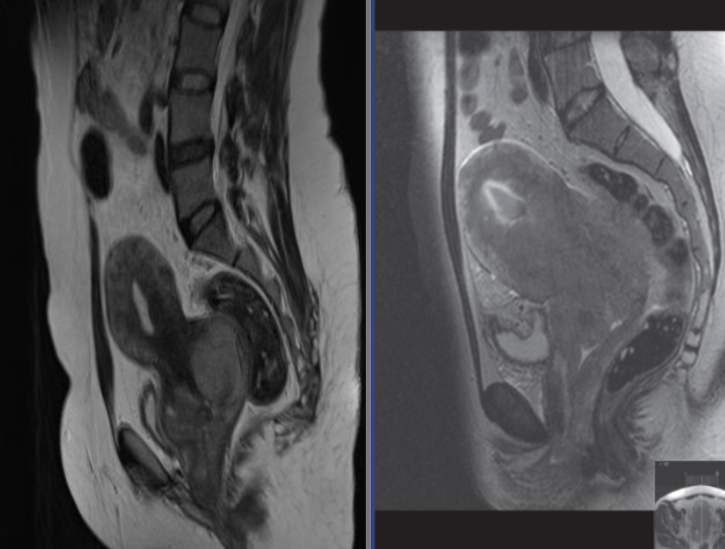

Two different cases. T2 weighted sagittal MRI showing carcinoma of

cervix